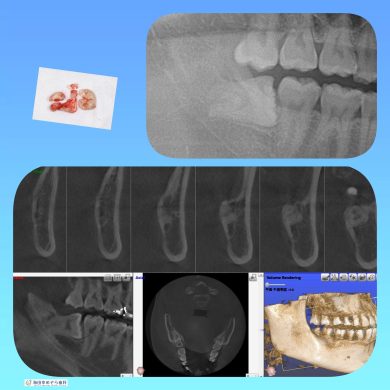

横向き親知らずの抜歯症例

院長はこのような横向きに埋まっている抜歯ケースも

1000症例以上の手術実績あり☆

横に埋まっている場合はCT撮影で安心です☆